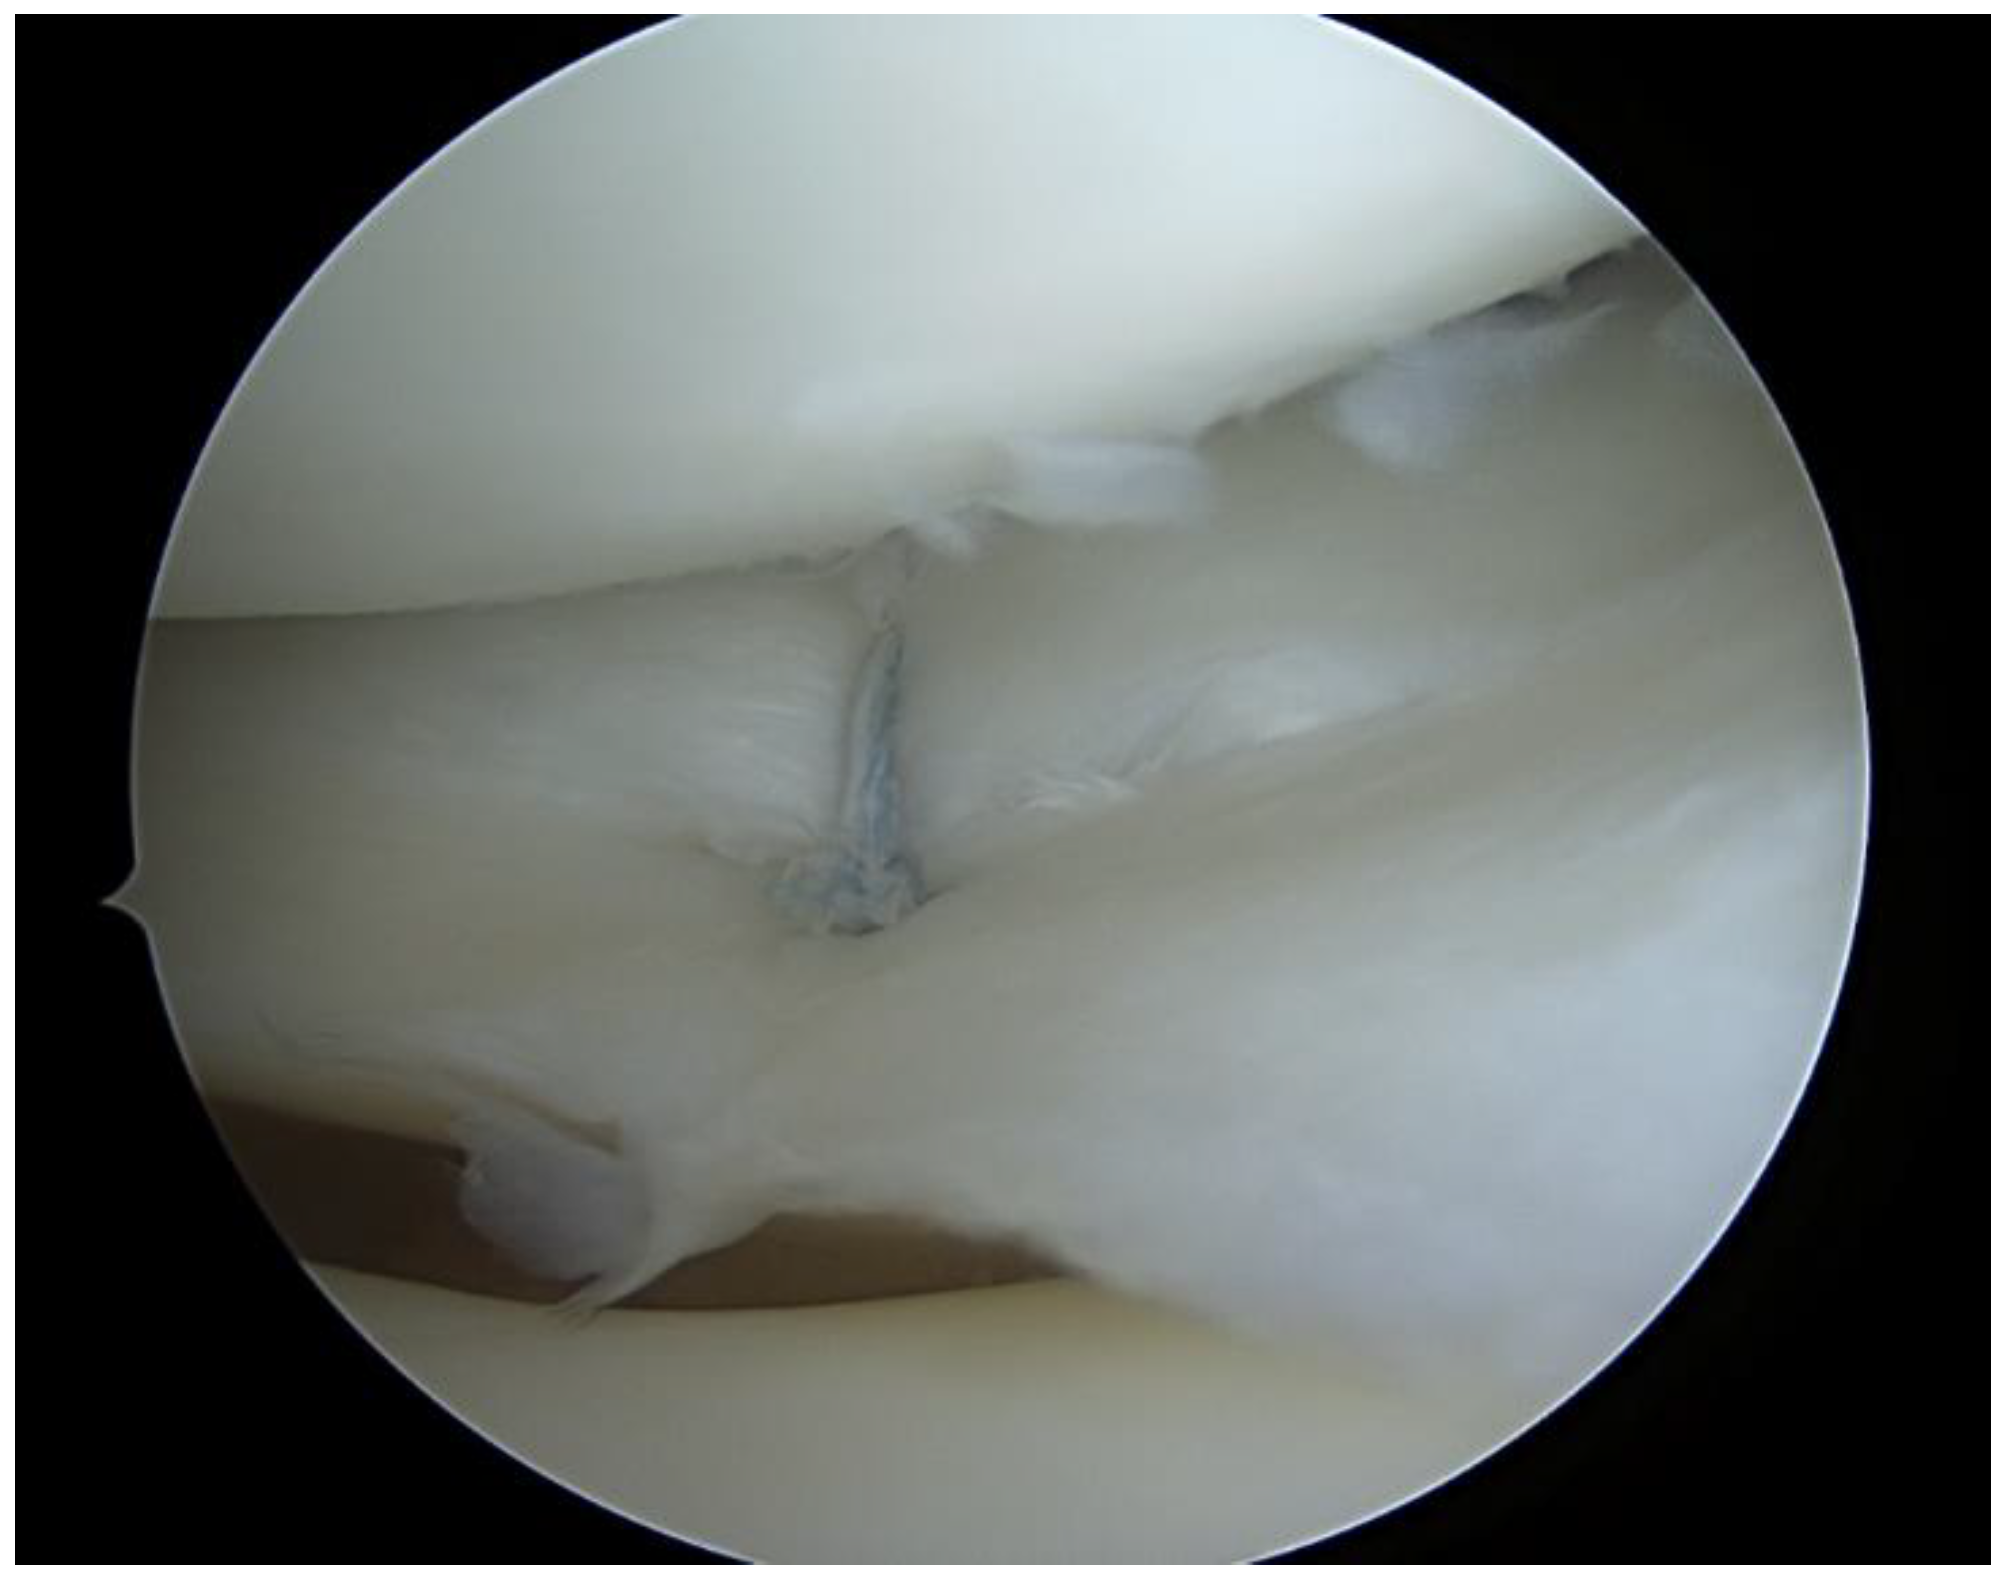

2.2. Surgical Technique